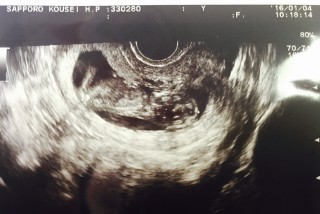

母子手帳を貰ってから初めての妊婦健診でした(*Ü*) 相変わらずつわりが酷くて、特に夕方〜夜は吐き気と頭痛がピークで動けません(><)(´;_;`) 赤ちゃんはちょうど起きてたみたいで元気いっぱいに動きまくってました! BPD2cm、CRL4.9cmでした(*ˊᵕˋ*) 次は4週間後!性別わかるかな〜(っ ॑꒳ ॑c)✩

寝てるみたいです♡大きさは6.45センチくらいでした!